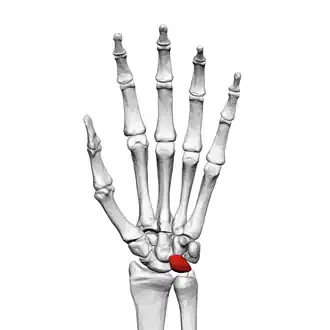

![]() Left hand anterior view (palmar view). Lunate bone shown in red. | |

The lunate bone (semilunar bone) is a carpal bone in the human hand. It is distinguished by its deep concavity and crescentic outline. It is situated in the center of the proximal row carpal bones, which lie between the ulna and radius and the hand. The lunate carpal bone is situated between the lateral scaphoid bone and medial triquetral bone.

The lunate is a crescent-shaped carpal bone found within the hand. The lunate is found within the proximal row of carpal bones. Proximally, it abuts the radius. Laterally, it articulates with the scaphoid bone, medially with the triquetral bone, and distally with the capitate bone. The lunate also articulates on its distal and medial surface with the hamate bone.[2]: 708 [3]

The proximal surface of the lunate bone is smooth and convex, articulating with the radius. The lateral surface is flat and narrow, with a crescentic facet for articulation with the scaphoid bone. The medial surface possesses a smooth and quadrilateral facet for articulation with the triquetral bone. The palmar surface is rough, as is the dorsal surface. The dorsal surface is broad and rounded. The distal surface of the bone is deep and concave.[4]